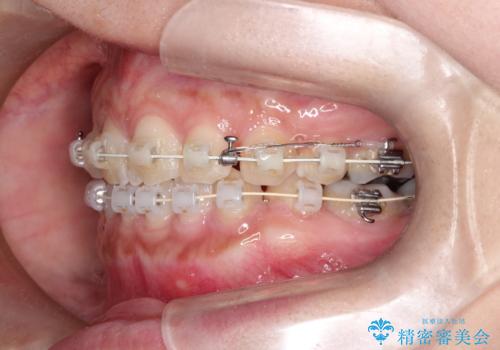

- 矯正装置

- 審美装置

- 2年2ヶ月

- 10-30回